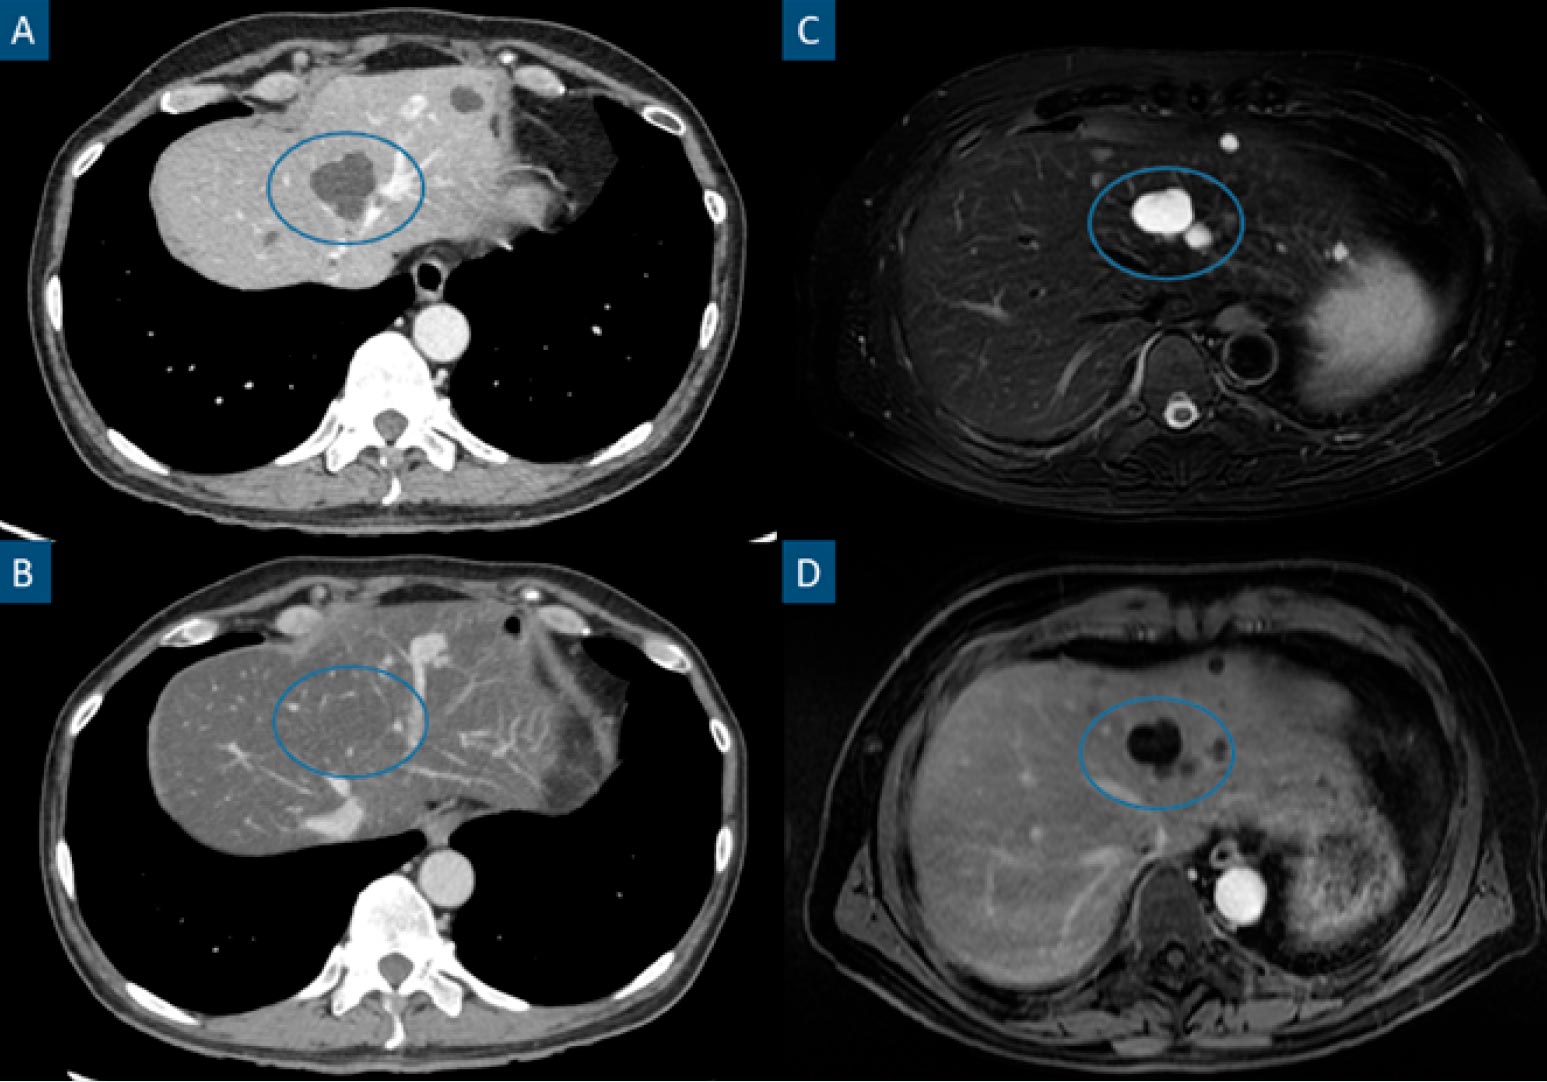

CT has shown limitations in the detection of liver metastases under 1 cm, especially after neoadjuvant chemotherapy and associated diffuse fatty infiltration of the liver18 (Fig. 2).

Figure 2: Steatotic liver hiding previously easily identifiable hypodense hepatic lesions in CT. Axial contrast-enhanced portal phase CT images (A and B), axial fat-suppressed T2-weighted image (C) and axial contrast-enhanced portalphase T1-weighted image (D). Patient with a stage IV clear cell renal cell carcinoma. A shows a hepatic cyst (circle), characterized by a hypodense, non-enhancing and well-marginated hepatic lesion. The patient underwent a chemotherapy cycle after the previously mentioned study and B was a follow-up CT performed 6 months later. B shows a noticeably steatotic liver, characterized by a low parenchymatous density. In this setting, hypovascular lesions such as cysts or most metastatic lesions may become inconspicuous as is the case in B. MRI (C and D) easily identify these lesions (circles) in the steatotic liver as T2 hyperintense non-enhancing lesions.